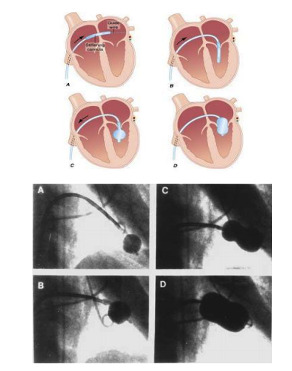

- Nong van hai lá bằng bóng:

+ Đưa bóng nong (đã được làm căng) vào nhĩ trái dựa trên wire vòng,

+ Dùng que lái bóng đưa bóng nong qua lỗ van hai lá

+ Bơm bóng nong từng bước để tách mép vao hai lá, đánh giá áp lực nhĩ trái, khả năng bị hở van hai lá tăng… để quyết định tăng cỡ bóng tối ưu

Hình 15.1: Quy trình bong van hai lá bằng bóng Inoue